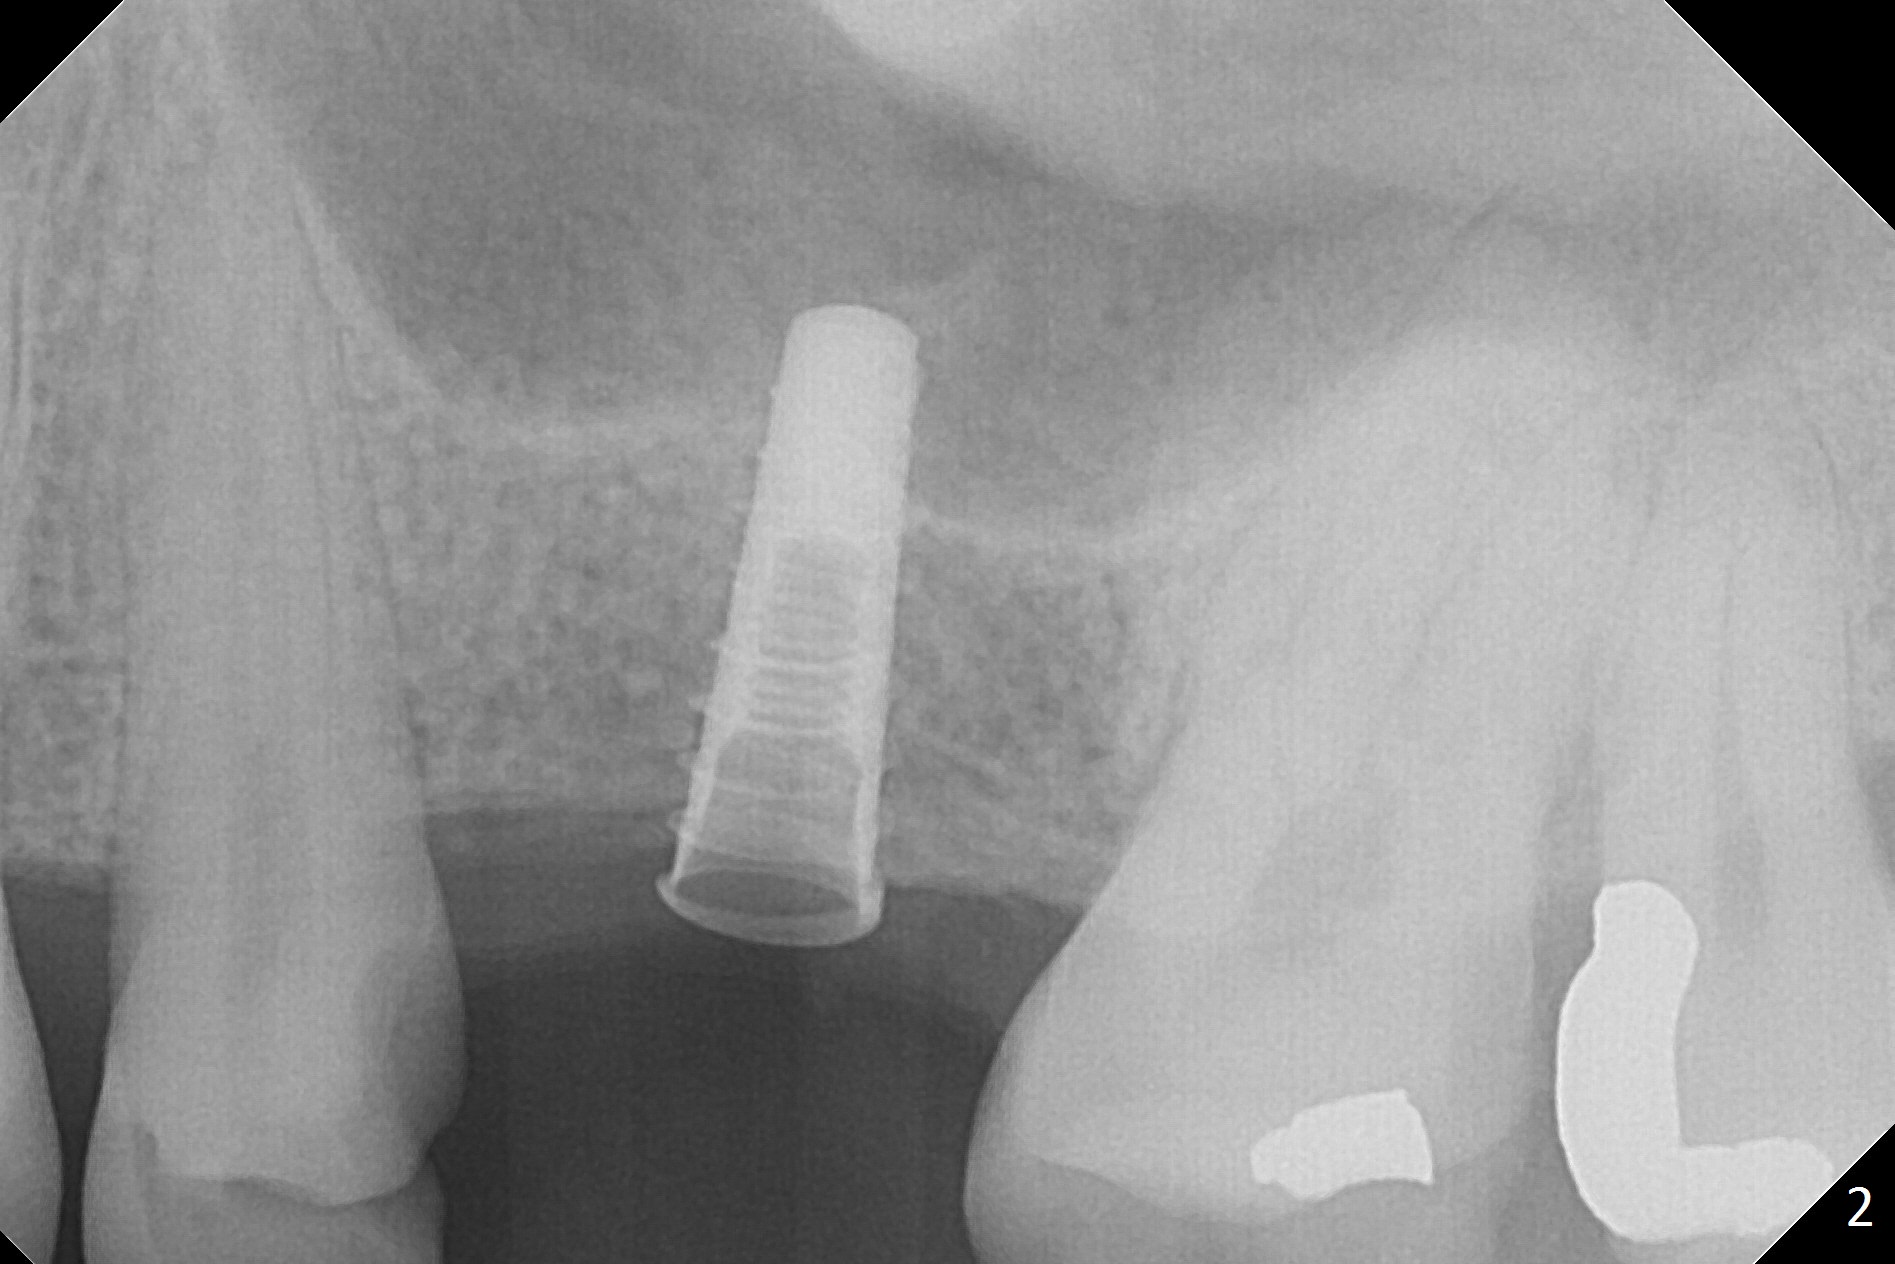

While the base of the ridge at #14 is wide, the top is moderate. IBS Magic Split is applied to gain access and test bone density (flapless). In fact the bone is hard. A 1.6 mm pilot drill is used for 9 mm (gingival level), followed by insertion of a parallel pin (Fig.1). Following Magic Expander 3.0 mm and Magic Drill 3.8 mm for ~ 11 mm (with empty feeling without air leak), a 4x11 mm dummy implant is placed with 25 Ncm (Fig.2). After insertion of a 4.5x11 mm dummy implant at 9 mm (35 Ncm; for further bone expansion), one piece of PRF plug and 1 piece of PRF membrane are pushed into the osteotomy, followed by allograft mixed with autogenous bone for sinus lift and placement of a 5x9 mm implant (Fig.3,4 with insertion torque >50 Ncm). A 6x4(2) mm abutment is placed for fabrication of an immediate provisional (Fig.5 P). There is no nasal hemorrhage postop. PRF membrane and plug are used to prevent and repair sinus membrane perforation and facilitate wound healing. There is mild bone resorption at the crest 11 months postop (Fig.6,7). The bone resorption seems to be worse 8 months post cementation (Fig.8,9); in fact the abutment screw is loose.